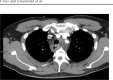

Esophageal perforation is a rare condition that is commonly missed. Male gender and alcohol use are predisposing risk factors. Most of the cases are iatrogenic or traumatic; nonetheless, spontaneous cases are not uncommon. It typically occurs after vomiting or straining as the increased intra-abdominal pressure transmits into the esophagus and results in the tear. One of the main complications is acute bacterial mediastinitis from contamination with esophageal flora. This condition can be life-threatening because it is very frequently misdiagnosed and appropriate management is often delayed.A 49-year-old man presented with worsening sudden-onset interscapular back pain that then changed to chest pain with odynophagia and was found to have fever and leukocytosis.Chest computed tomography revealed signs of mediastinitis with possible esophageal perforation. He reported symptoms started 2 days ago after lifting of heavy objects. Empiric antimicrobial was begun with conservative management and avoidance of oral intake. Barium esophagram and esophagogastroduodenoscopy revealed no signs of perforation or inflammation. His symptoms resolved and he gradually resumed oral intake. Blood cultures grew Methicillin-sensitive Staphylococcus aureus and he was discharged on appropriate antibiotics for 4 weeks. He did well on follow-up 3 months after hospitalization.The case highlights the importance of considering esophageal etiologies of chest pain.